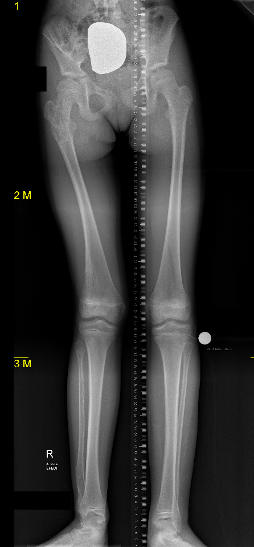

Growth disturbance

- leg length discrepancy

- bowing

Leg length discrepancy

Hosny et al J Pediatr Orthop B 2023

- 13 patients with LLD and angular deformity

- intralesional osteotomy and distraction osteotomy

- in conjunction with guided growth

- good correction and bone regeneration

Elbow and wrist bowing